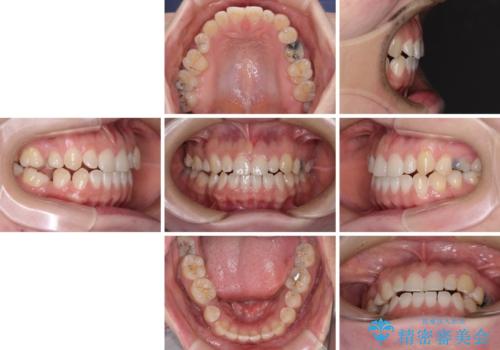

- 隙間の多い歯列や傾斜した奥歯、むし歯の酷い残存乳歯を気にして来院された患者様です。

歯列はワイヤー矯正にて改善することとしましたが、上下歯列にも隙間があったので、舌の突出癖を改善するトレーニングを徹底的に行うこととしました。

傾斜した下顎の奥歯は、矯正治療にてまずは歯軸を改善させ、隙間が閉じられるようであればそのままに、閉じられないようであればインプラント治療を行うこととしました。

上顎のむし歯の酷い残存乳歯は抜歯をし、矯正治療の途中でインプラントを埋入、矯正治療後に補綴治療を行うこととしました。

舌の突出癖改善のトレーニングが全くうまくできず、治療期間が長期化しました。

早く治療を終えたいとの要望があり、トレーニング次第と伝えるとようやく練習をするようになり、その後は速やかに上下の隙間が改善されました。